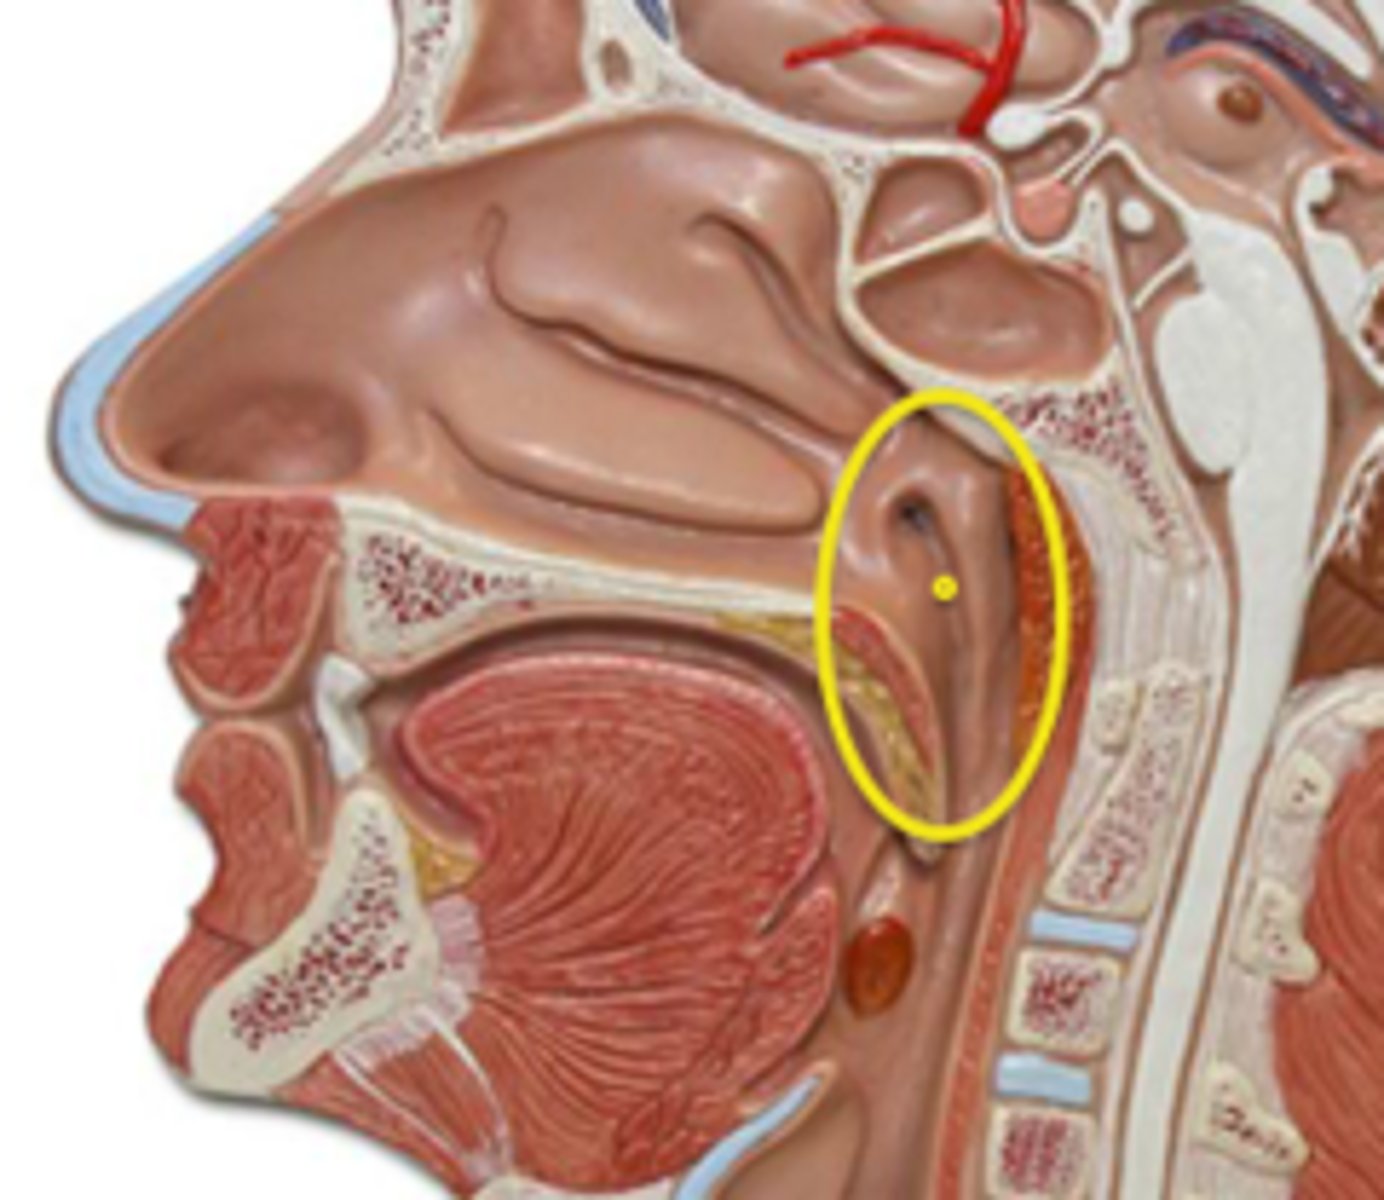

Nasal Cavity

Turbinates (Conchae)

- Bones that protrude into the nasal cavity- that increases surface area for filtering dust and dirt particles by the mucous membrane

- There's an inferior, middle, and superior one (2.), 3.), 4.))

Olfactory Region

A dime-sized area at the top of each nasal cavity that houses sensors responsible for smell (1.))

Hard (Bony) Palate

Anterior palate portion that is supported by the palatine processes of the maxillae and the palatine bones (8.))

Meatuses

- Constricted passageways in the nasal cavity that produce air turbulence

- There's an inferior, middle, and superior one

(5.), 6.), 7.))

Soft Palate

Posterior palate portion, not supported by bone (9.))

Nasopharyx

The portion of the pharynx that extends from the nostrils to the soft palate

Oropharynx

Central portion of the pharynx between the roof of the mouth and the upper edge of the epiglottis

Tonsils

Masses of lymphatic tissue in the back of the oropharynx

3 Tonsils in the Mouth

- Palatine

- Adenoid

- Lingual

Palatine Tonsil

One of a pair of almond-shaped masses of lymphatic tissue in the oropharynx

Adenoid Tonsil

Pharyngeal tonsil

Lingual Tonsil

Tonsil located at the base of tongue